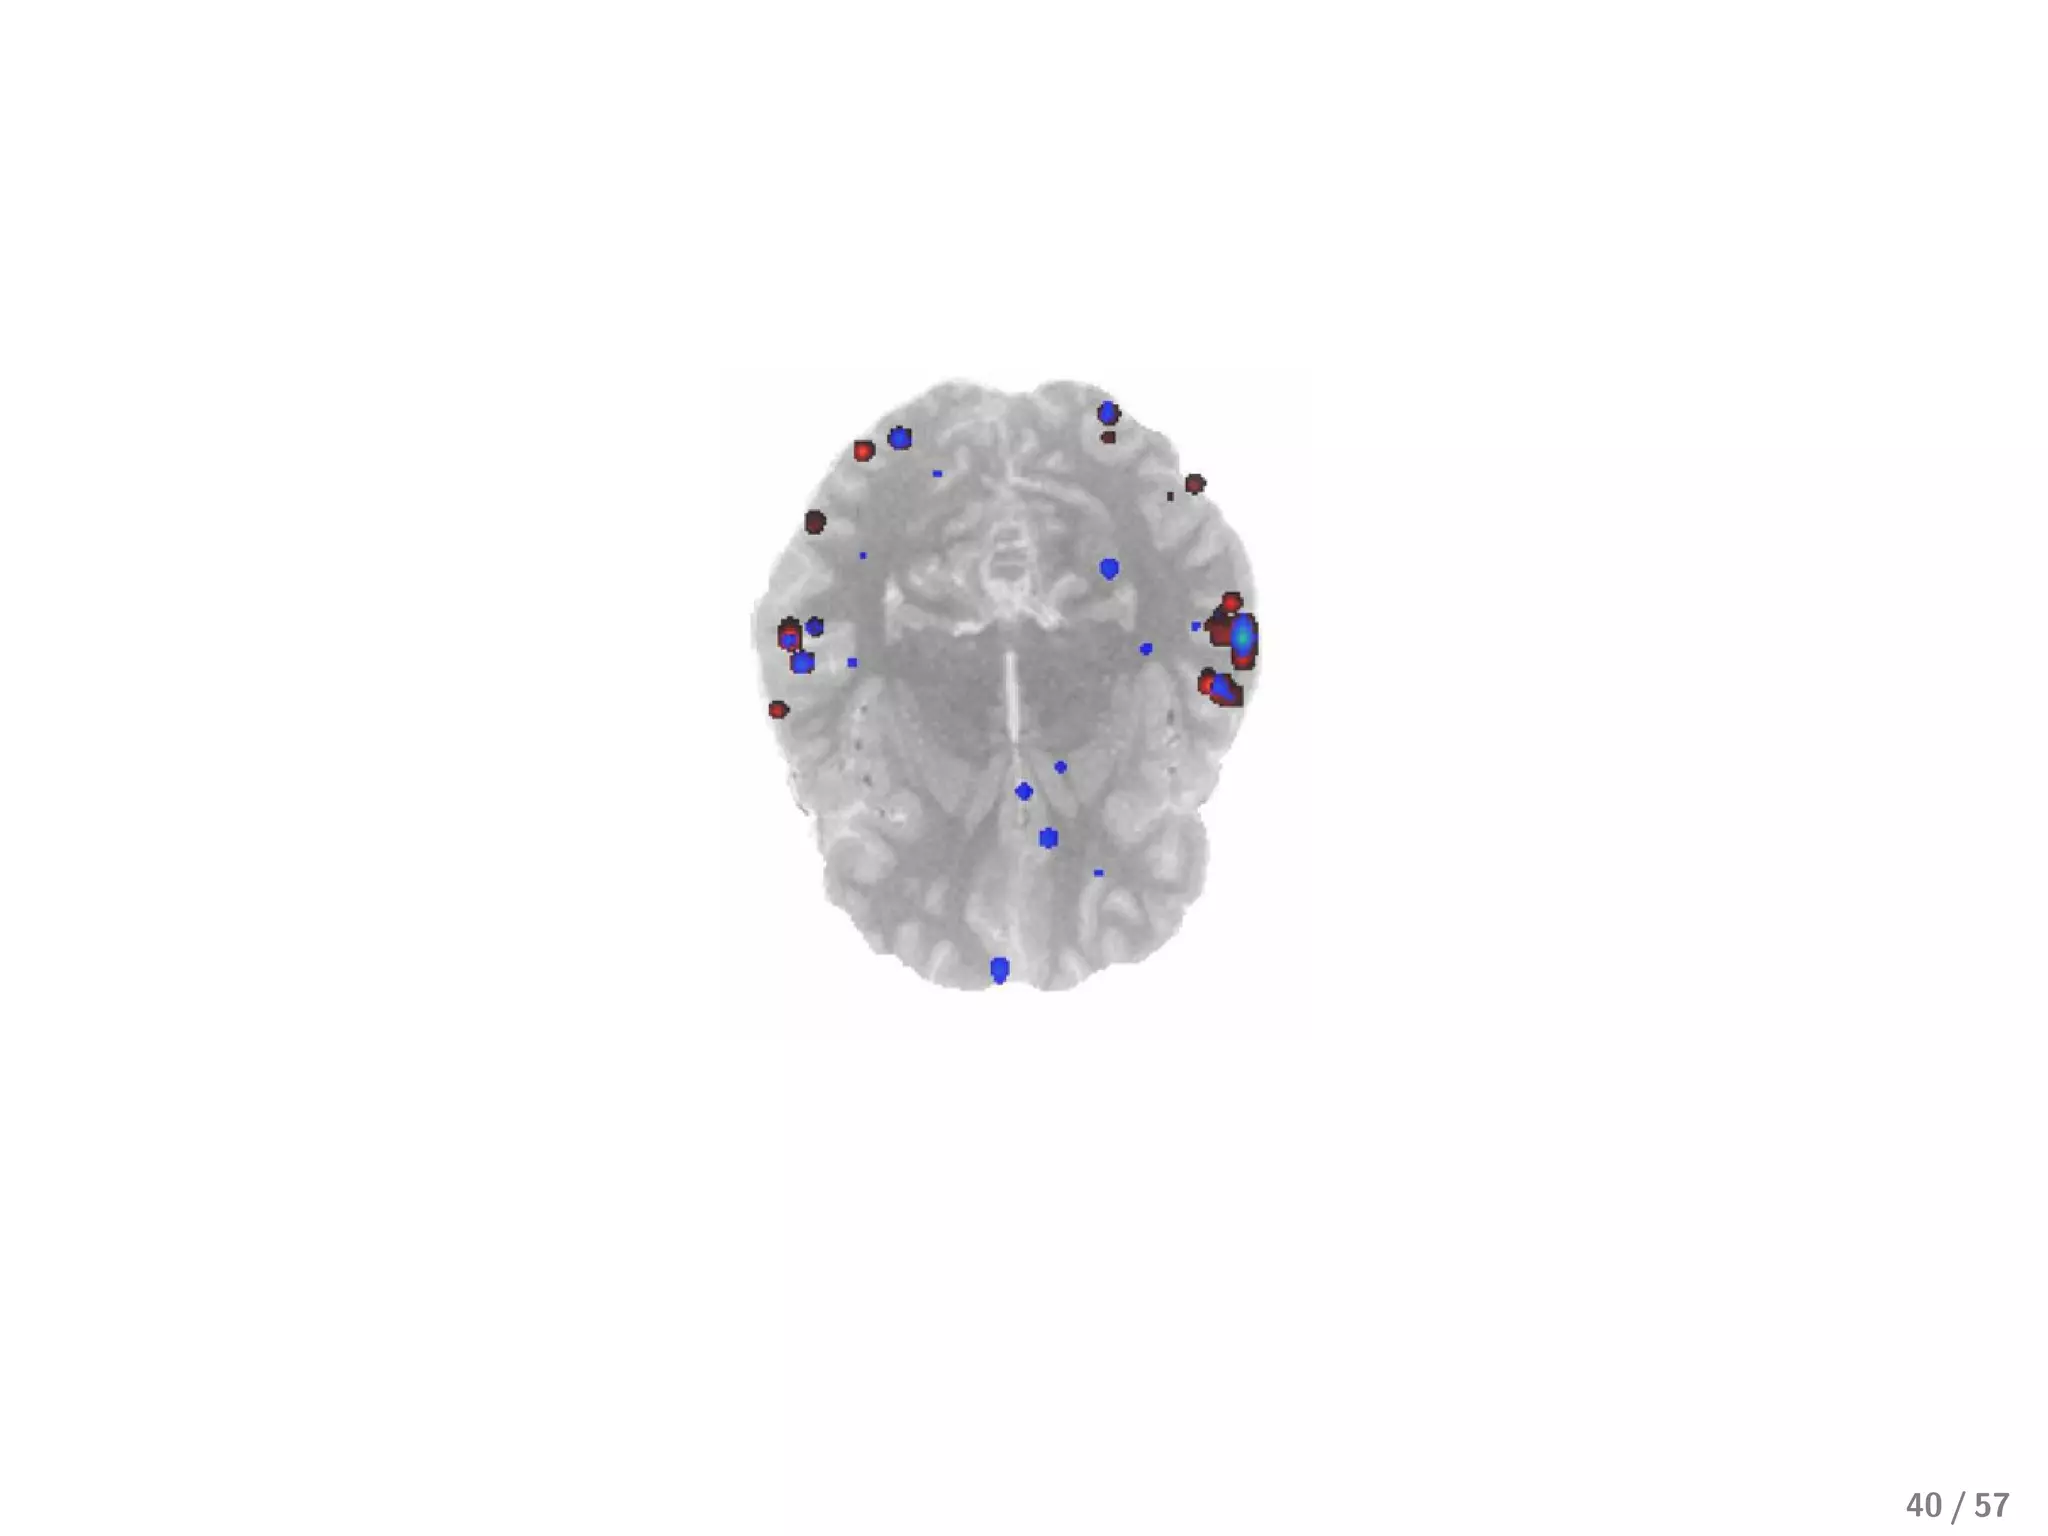

For MVPA, L1 sparse solutions are, sadly, too sparse

39 / 57

From neurology, we know we should expect large clusters of voxels

Best current approach: mix L1 and L2

In the Elastic Net, we minimize (y − Xβ)2 + λ1 |β| + λ2 β 2